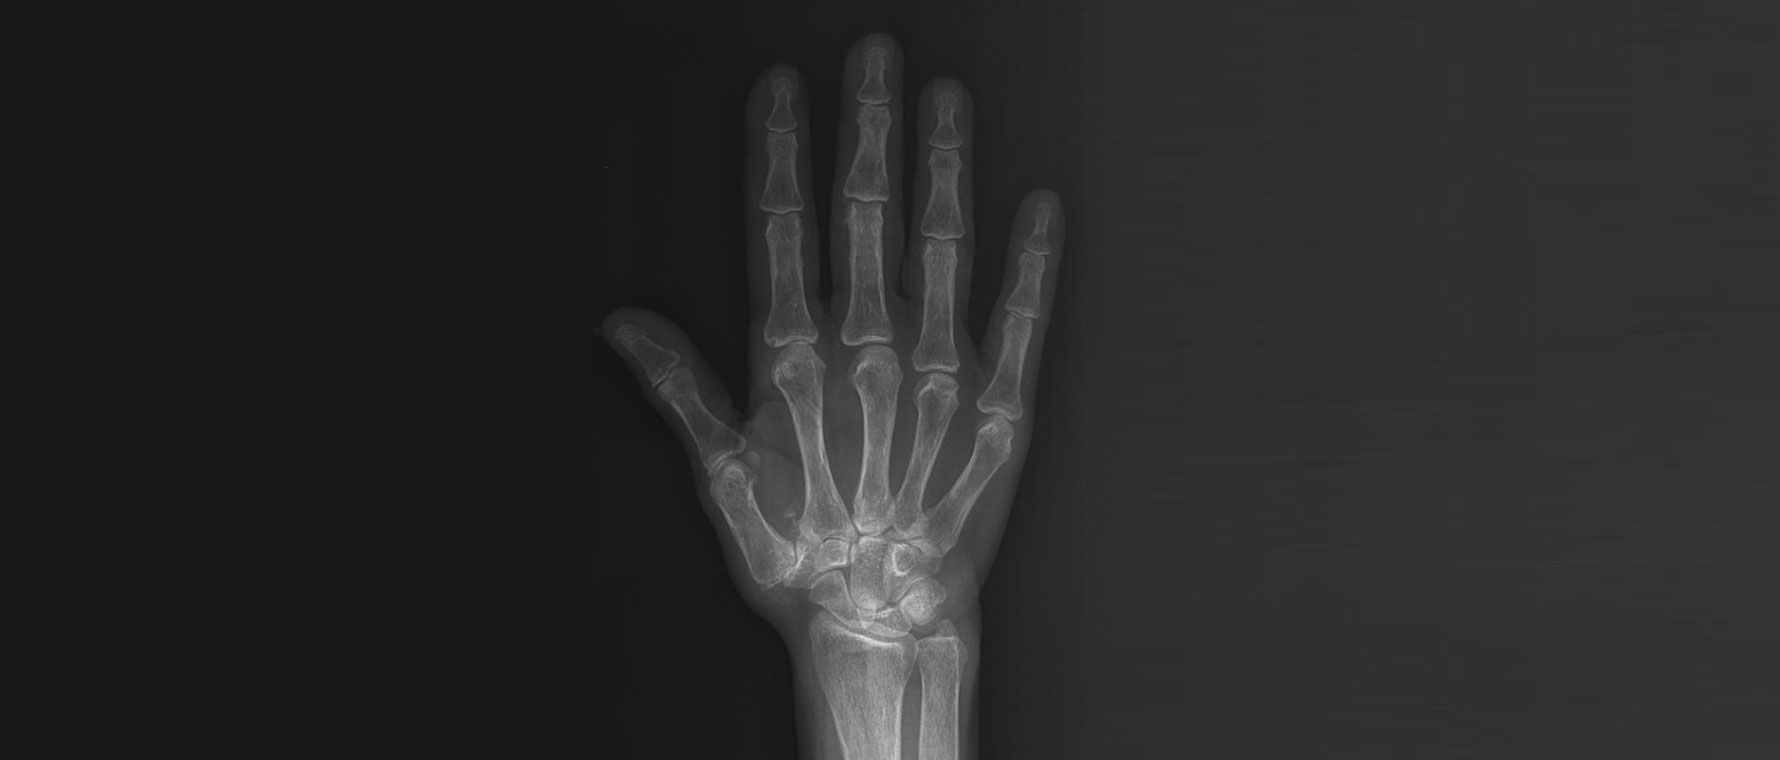

Parmak Eklemlerinde Kireçlenmeler

Parmak eklemlerinde kireçlenme, eklem kıkırdağının zamanla aşınması sonucu ortaya çıkan bir durumdur. Genellikle yaşla birlikte gelişir, ancak geçirilmiş travmalar ve yoğun kullanım da etkili olabilir. Hastalarda ağrı, şişlik, sertlik ve parmaklarda şekil değişikliği görülebilir. Sabah tutukluğu sık bir şikâyettir. Tanı muayene ve röntgen ile konur. Tedavide ağrı kesici ilaçlar, egzersizler, atel kullanımı ve eklem içi enjeksiyonlar uygulanabilir. Şikâyetleri ileri düzeyde olan hastalarda cerrahi seçenekler gündeme gelir.